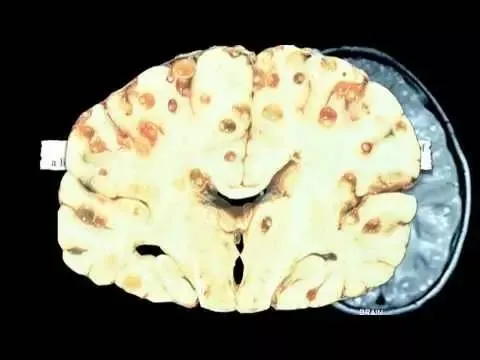

朊病毒,准确地说应该叫朊毒体,是一种由异常折叠的蛋白质组成的致病因子。它能够引发一系列致命的神经退行性疾病,包括疯牛病、库鲁病和克雅氏病等。这些疾病的特点是大脑组织出现海绵状空洞,导致患者出现痴呆、肌肉抽搐等症状,最终死亡。